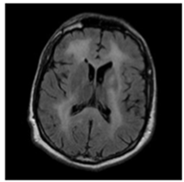

| No Tumor | Glioma Tumor | Meningioma Tumor | Pituitary Tumor | |

| Brain MRI Images |  ![]()  |  ![]()  |  ![]()  |  ![]()  |